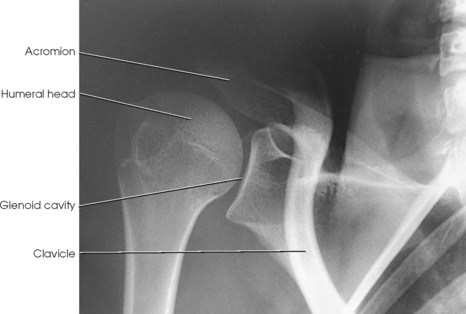

Structures shown: The image shows the bony and soft structures of the shoulder and proximal humerus in the anatomic position (Figs. 5-14 to 5-16). The scapulohumeral joint relationship is seen.

External rotation: The greater tubercle of the humerus and the site of insertion of the supraspinatus tendon are visualized (see Fig. 5-14, A).

Neutral rotation: The posterior part of the supraspinatus insertion, which sometimes profiles small calcific deposits not otherwise visualized (see Fig. 5-14, B), is seen.

Internal rotation: The proximal humerus is seen in a true lateral position. When the arm can be abducted enough to clear the lesser tubercle of the head of the scapula, a profile image of the site of the insertion of the subscapular tendon is seen (see Fig. 5-15).